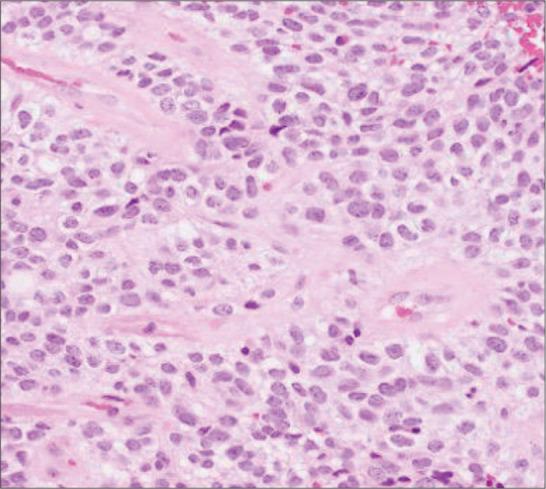

A 55-year-old woman presented with seizures and ataxia 15 years after an initial resection of a clear cell ependymoma, Grade 2. Imaging demonstrated an enhancing right paracentral mass and the patient underwent biopsy and resection. Microscopic analysis showed regions of the tumor with morphological and immunohistochemical features typical of ependymoma, including perivascular pseudorosettes and focal dot- like epithelial membrane antigen positivity, as well as high-grade features. In addition, the neoplasm contained large nodular regions of clear cells exhibiting extensive synaptophysin immunoreactivity, suggestive of neural differentiation, and only focally positive immunoreactivity for glial markers. Electron microscopy showed poorly formed and ill-defined junctional complexes, but no cilia, microvilli, or dense granules were seen. Molecular profiling revealed the presence of a fusion between (previously known as and fusion.

一名55岁女性在初次切除2级透明细胞室管膜瘤15年后出现癫痫发作和共济失调。影像学检查显示右侧中央旁有一强化肿块,患者接受了活检和切除术。显微镜分析显示肿瘤区域具有室管膜瘤典型的形态学和免疫组化特征,包括血管周围假菊形团和局灶性点状上皮膜抗原阳性,以及高级别特征。此外,肿瘤包含大片透明细胞结节区域,表现出广泛的突触素免疫反应性,提示神经分化,而胶质标志物仅呈局灶性阳性免疫反应。电子显微镜显示连接复合体形成不良且界限不清,但未见纤毛、微绒毛或致密颗粒。分子谱分析显示存在(以前称为与融合。